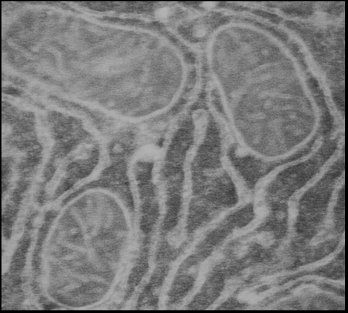

3.6 Иммунноэлектронная микроскопия

Ткань печени и сердца фиксировали в 4%-ном растворе параформальдегид/0.05% глутаровый альдегид в PBS – буфере (16.7 мМ Na2 HPO4 · 12 H2 O, 3.3 мМ KH2 PO4 , 150 мМ NaCl, рН 7,4) в течение 4 ч при 4°С. Обезвоживание в спиртах и пропитку образца смолой LR-White (Sigma, USA) проводили при 4°С. Полимеризацию смолы осуществляли под ультрафиолетом в течение 48 часов при комнатной температуре. Ультратонкие срезы готовили на ультратоме UC6 (Leica, Германия) и помещали на золотые сеточки, покрытые формваровой пленкой и укрепленные углем (Agar). Неспецифическое окрашивание блокировали обработкой раствором, содержащим 3% БСА и 0.5% желатина в течение 1ч. Все дальнейшие процедуры проводили в PBS содержащем 1% БСА и 0.01% тритон Х-100. После каждой инкубации образцы отмывали PBS- буфером, содержащим 0.1% тритон Х-100 и 0.1% глицин и затем в растворе БСА и желатина в течение 20 мин [18]. В качестве первичных антител были использованы полученные нами антитела к митохондриальному К+ -транспортирующему белку (в разведении 1:100), инкубацию с которыми проводили в течение ночи при 4°С. После тщательной отмывки сеточки с образцами помещали на каплю вторичных антител, меченных коллоидным золотом с размером гранул 10 нм (Anti-RabbitIgG, Sigma, USA) и инкубировали в течение 2 часов при комнатной температуре. После отмывки образцы окрашивали уранилацетатом и цитратом свинца и просматривали под электронным микроскопом Tesla BS-500 (Чехословакия). Специфичность метода проверяли заменой первичных антител на буфер.